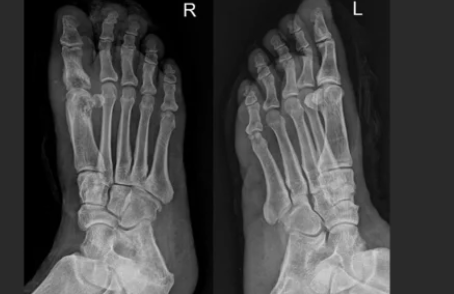

3️⃣ 무지외반증(엄지발가락 변형)

- 엄지발가락이 휘면서 발바닥 압력이 특정 부위에 집중

- 발바닥 앞쪽(중족골 부위)에 굳은살·통증 동반

- 원인: 하이힐·폭 좁은 신발, 유전적 요인